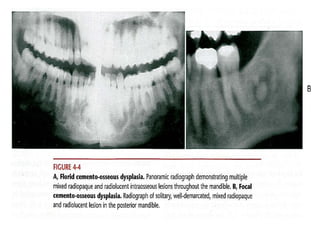

Periapical cemento-osseous dysplasia